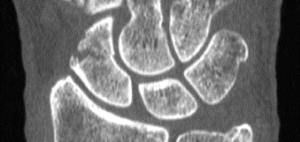

CT assessment of patients casted for a non-displaced scaphoid fracture shows union occurring at approximately 7.5 weeks, with a majority of fractures healing in less than 6 weeks, according to a 2016 study by Ruby Grewal et al. Similar studies using plain X-Ray demonstrated union time to be anywhere between 10 – 24 weeks. The authors noted the union time on CT may even be overestimated because the majority of patients’ first CT scan after casting was not until 6 weeks.

In a previous study, Professor Timothy Davis wrote CT studies demonstrate healing of a non-displaced fracture treated with a plaster cast can occur in as little as 4 weeks. If a fracture is displaced less than 2 mm, Davis said those CT studies suggest a plaster cast for 8 – 12 weeks.

CT is ideally performed for all scaphoid waist fractures in the first week after injury to classify whether they are displaced or non-displaced, said Professor Davis, an orthopedic surgeon at Woodthorpe Hospital in Nottingham, UK said in his research paper.

By using CT as a baseline, researchers at the Roth/McFarlane Hand and Upper Limb Center in London said they were able to identify fractures which may have appeared non-displaced on X-Ray, but were actually minimally displaced.

“We feel that the added visualization of CT over plain radiography enables the surgeon to properly select which fractures are appropriate for non-operative cast treatment with an expected high degree of union,” the researchers said in a study published in The Open Orthopaedics Journal.

Out of the research setting, routine CT scans of scaphoid fractures may not be practically feasible, Professor Davis wrote.

“I appreciate that [routine CT assessment of scaphoid fractures] is impossible in many centers at the present time but it should become increasingly possible in the future,” Professor Davis wrote in the medical journal “Annals of the Royal College of Surgeons of England” in 2013.

Fifteen percent of acute fractures of the scaphoid waist fail to unite if treated non-operatively in plaster, resulting in a persistent loss of function, according to the 2013 article. Plain X-Rays do not clearly show fracture features such as displacement and communition. Previous inter-observer studies have shown radiographs of scaphoid fractures are neither sensitive nor specific.